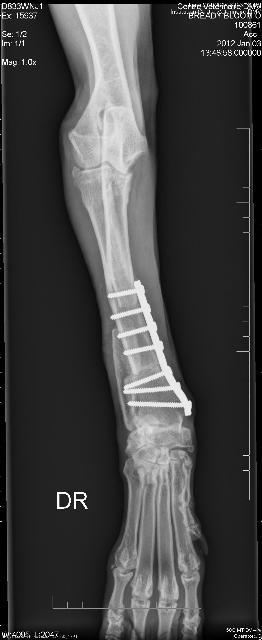

Her radius curvus syndrome was addressed, a bloat survivor and nothing ever held her back!